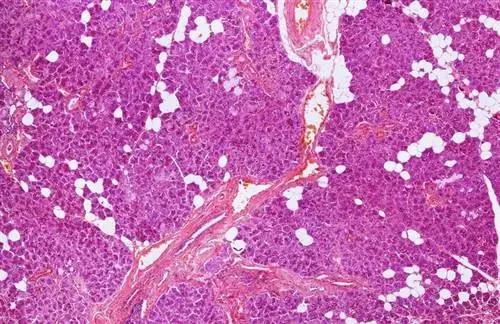

6/8 Муковисцидоз

кистозный фиброз

Кистозный фиброз - это генетическое заболевание, которое влияет на работу экзокринных желез. В результате этого заболевания в органах появляется густая слизь. Наиболее заметно поражаются легкие, что приводит к хроническому бронхолегочному заболеванию. Кистозный фиброз лечится только симптоматически, что в основном сводится к антибиотикотерапии, ингаляциям, физиотерапии и оксигенотерапии. Люди, страдающие этим заболеванием, обычно доживают до двадцати лет в Польше.